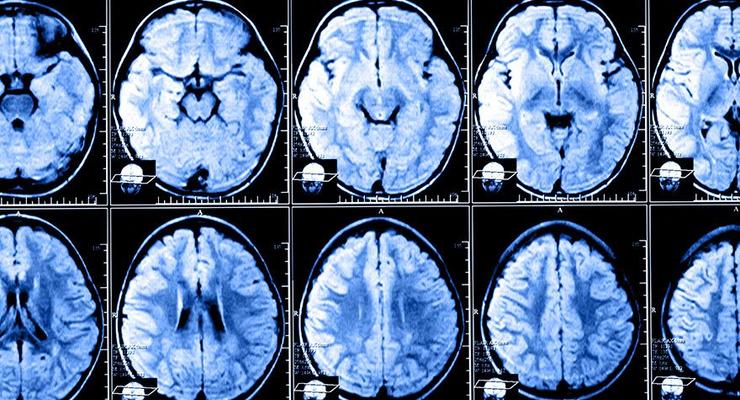

MS (Multiple skleroz) hastalığı, hem dünyada hem de Türkiye'de önemli bir sağlık sorunu olarak kabul ediliyor. Türkiye'de 35 bin kadar genç insanın etkilendiği hastalık hakkında internet üzerinde fazlasıyla bilgi kirliliği bulunuyor. Bu noktadan hareketle yola çıkan Hacettepe Üniversitesi Nöroloji Ana Bilim Dalı Öğretim Üyesi Prof. Dr. Rana Karabudak, MS hakkındaki gerçekleri açıklıyor.

İnternet üzerindeki bilgi kirliliğini önlemek için hastaların, hekimlerinden, yani ilk elden bilgi almasını önerdiklerini belirten Prof. Dr. Karabudak, “MS (Multiple skleroz) akıl hastalığı ya da ruhsal bir hastalık değildir. Mutlaka ilerleyici olacak ya da özürlülükle telaffuz edilecek bir hastalık da değildir” dedi. Prof. Dr. Karabudak'a göre, MS hastalığının erken dönemde yakalanması ve tanı konularak tedavinin başlanması, hastalıkla mücadelede büyük önem taşıyor.

Teknolojinin desteğiyle gelişen tanı yöntemlerinin hastalığı erken dönemde yakalama şansını artırdığını belirten Prof. Dr. Karabudak, engellilik riski taşıdığı için hem rehabilitasyon hem belirtilere yönelik tedaviler ile koruyucu tedavilerin tamamlanmasının önemine değindi.